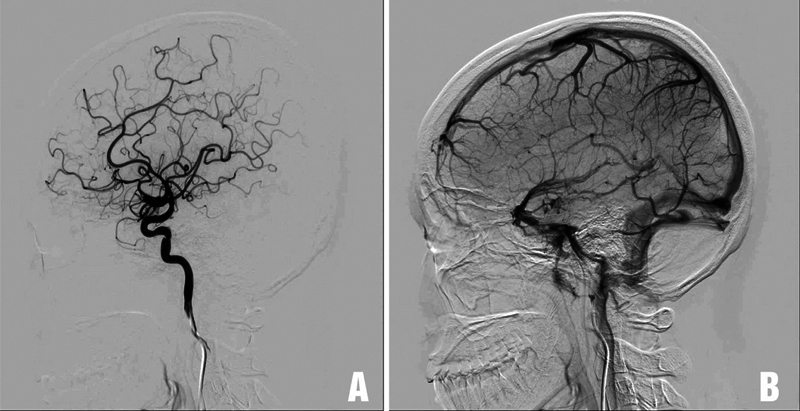

Flow diverter (FD) is often the first-line treatment for giant internal carotid artery aneurysms, with a high rate of aneurysm occlusion. However, up to 10% of giant cerebral aneurysms increase in size after FD treatment. Surgery is usually considered if the giant internal carotid artery aneurysm continues to enlarge and cause compression. We report a case of a giant internal carotid artery aneurysm that continued to increase in size after FD treatment and was subsequently treated surgically. We also review the literature on the management of giant cerebral aneurysms that increased in size after FD. A 41-year-old female patient was diagnosed with a right giant internal carotid artery aneurysm and was initially treated with FD. After FD, the patient's vision in the right eye did not improve. Despite medical treatment, her vision continued to deteriorate. The patient presented at our hospital with reduced vision in both eyes. Magnetic resonance imaging and digital subtraction angiography with balloon test occlusion confirmed the presence of a giant thrombosed aneurysm in the right internal carotid artery, compressing the right optic nerve and optic chiasm. The patient underwent external carotid artery-middle cerebral artery bypass surgery using a radial artery graft, aneurysm sac dissection with thrombus removal, and reconstructive clipping of the aneurysm neck. After surgery, the patient's vision in both eyes improved immediately and did not develop any new neurological symptoms. Extracranial-intracranial arterial reconstructive surgery is a viable option for treating giant internal carotid artery aneurysms that have undergone FD treatment but continue to present with progressive mass effects.